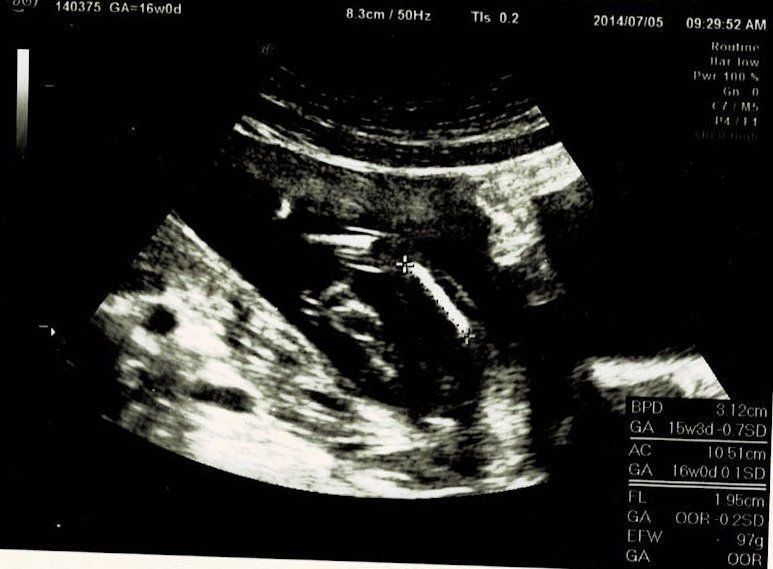

妊娠16週目エコー写真

初めての3Dエコーでした。今までレントゲンのようなエコー写真でしか赤ちゃんを見ていなかったので、芋虫みたいな見た目でも、「ちゃんと人間だ!」と不思議な気持ちになりました。エコーを見るたびに、「本当に人間ができているんだなぁ」と、毎回特別な気持ちになります。3Dエコーは、なんとなくこちらを見ている感じがして、かわいらしいと思ったり。手を口元に寄せて、すでに赤ちゃんらしい丸っこいポーズをしています。

この日は、BPD(頭の左右幅)、AC(おなかの周りの長さ)、FL(太ももの骨の長さ)を測って、赤ちゃんの育ちぐあいを見てくれました。このエコーは足の骨を測っているところです。足の指らしき骨も見えます。先生がスムーズに赤ちゃんの頭やおなか、足を探すのが面白く、測っている最中のエコーもずっと眺めていました。